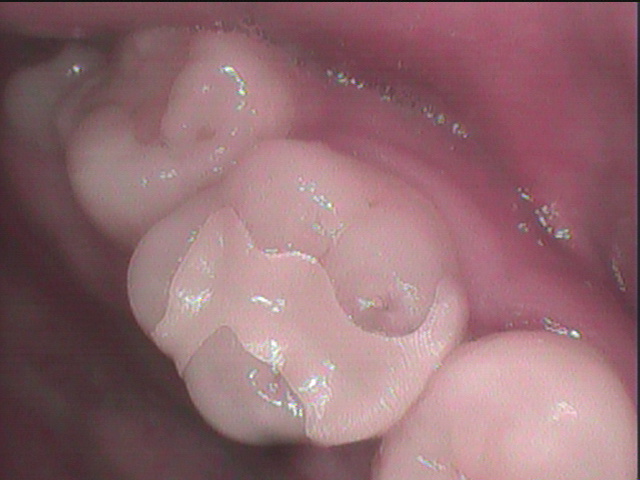

したがって本症例ではセラミックインレーである

e.maxインレーを選択しました・